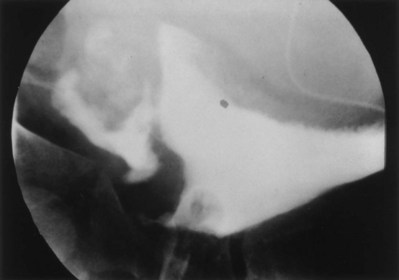

Some surgeons use leak point pressure to evaluate outflow resistance, the bladder pressure causing leakage per urethra, which can be determined during passive filling and Valsalva maneuver. Fluoroscopy can be informative during those events. The leak point pressure may be artifactually elevated by the urodynamics catheter in a small male urethra (Decter and Harpser, 1992). Much work remains to determine how well such measurable parameters correlate and identify which patients require a procedure on the outlet to achieve adequate continence.